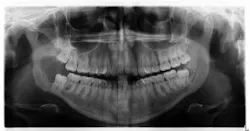

Clinical examination revealed inflamed tissue circa partially erupted No. 32 extending up to the distal of no. 2. The area intraorally was tender to palpation, but unremarkable extraorally. A panoramic X-ray was taken and a large radiolucent lesion was noted to extend from the distal of no. 1 to the distal of no. 32. A significant portion of bone destruction in the mandible was also observed. In addition, a radiolucency was seen distal to the crown on no. 17.

The patient was sent to surgery for enucleation and curettage of the lesion. Differential diagnoses included: unicystic ameloblastoma, odontogenic myxoma, and dentigerous cyst.

Our main concern was the extent of destruction—fracture potential and permanent paresthesia was extremely high. Following surgery, the patient was placed on a liquid diet for six to eight weeks. The specimen was sent to pathology. Diagnosis: dentigerous cyst. Follow-up over the course of the last year has proved to be promising—the bone has filled in, the patient has regained some feeling on the lower right side of her jaw and, thus far, there have been no recurrent or metastatic lesions observed. We are monitoring no. 17 and plan to remove it and the associated radiolucency when the bone has healed sufficiently in the right mandible.